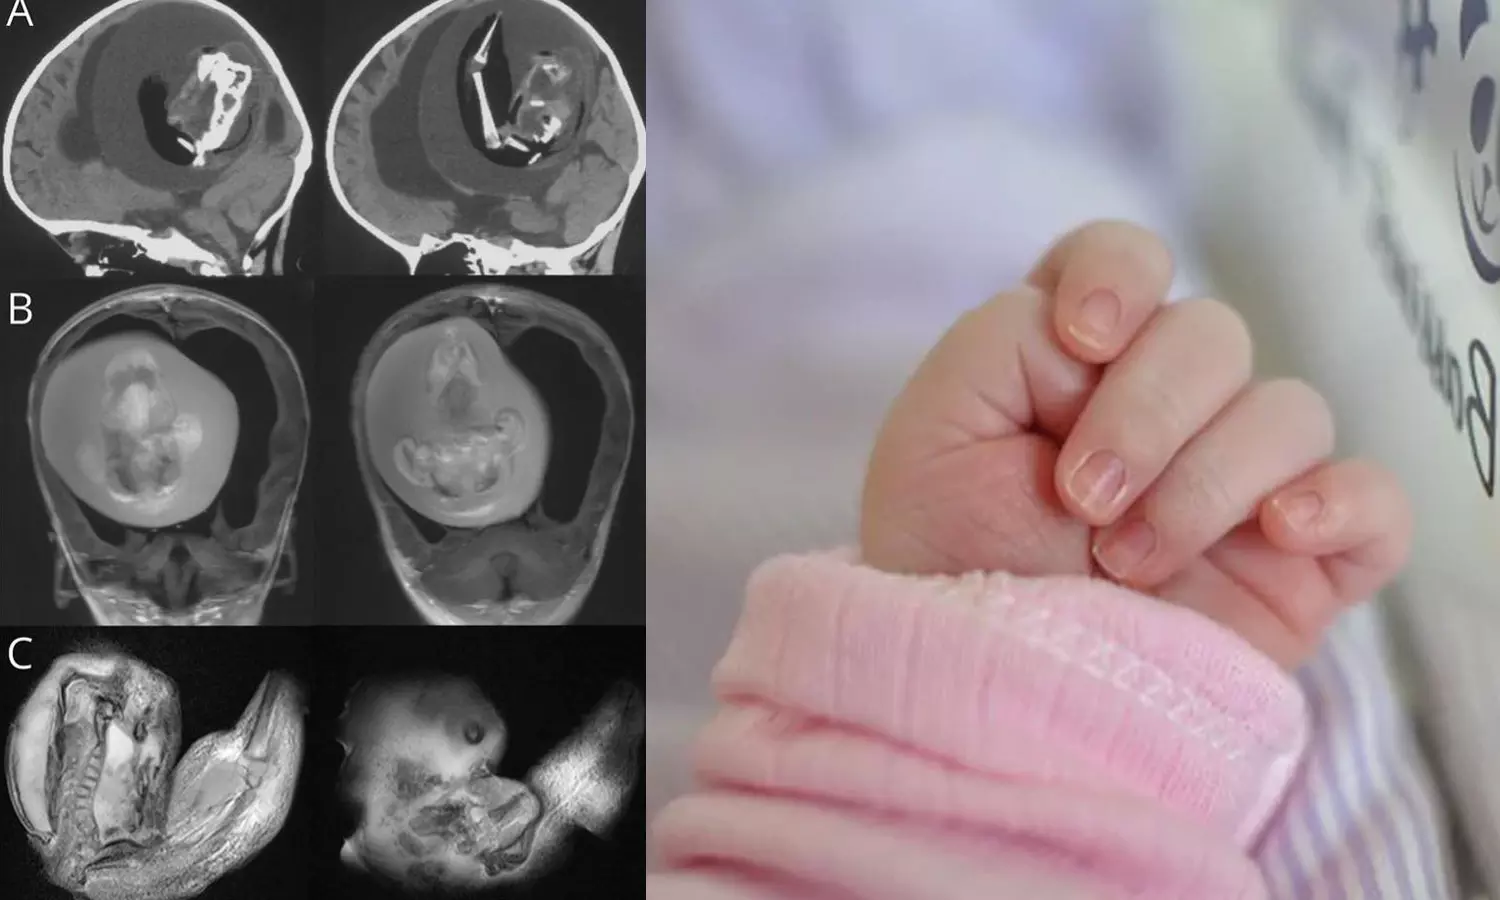

തല വലുതായ കുഞ്ഞിനെ ആശുപത്രിയിൽ പ്രവേശിപ്പിച്ചപ്പോൾ നടത്തിയ സ്കാനിങ്ങിലാണ് ഞെട്ടിക്കുന്ന വിവരം അറിഞ്ഞത്. ഇരട്ടയുടെ ഭ്രൂണത്തിന് കൈകാലുകളും എല്ലുകളും വിരലുകൾ പോലെയുള്ള മുകുളങ്ങളും വികസിച്ചതായി ഡോക്ടർമാർ പറഞ്ഞു.

ഇൻട്രാവെൻട്രിക്കുലാർ ഫീറ്റസ്-ഇൻ-ഫീറ്റൂ എന്നറിയപ്പെടുന്ന ഈ അവസ്ഥ ഗർഭാശയത്തിൽ ഇരട്ടകൾ കൂടിച്ചേരുമ്പോഴാണ് സംഭവിക്കുന്നതെന്ന് ഡോക്ടർമാർ പറയുന്നു. 'എന്നാൽ ഒന്നിന്റെ വളർച്ച മാത്രമേ കൃത്യമായി നടക്കുന്നുള്ളൂ'- മിയാമി ഹെറാൾഡ് റിപ്പോർട്ട് ചെയ്തു. ഒരു കുട്ടിയുടെ വയറ്റില് മറ്റൊരു ഭ്രൂണം വളരുന്ന അവസ്ഥയാണിതെങ്കിലും ചിലപ്പോഴൊക്കെ അത് തലച്ചോർ ഉൾപ്പെടെയുള്ളവയിലും ആവാം.

ഭ്രൂണത്തിന്റെ ജീനോം സീക്വൻസിങ് ഇത് ഒരു വയസുള്ള കുഞ്ഞിന്റെ ഇരട്ടയാണെന്ന് കണ്ടെത്തിയതായി പഠനം പറയുന്നു. ഇത്തരം കേസുകൾ ലോകത്ത് വളരെ അപൂർവമായി മാത്രമേ കാണപ്പെടുന്നുള്ളൂ, 10 ലക്ഷം കുട്ടികളിൽ ഒരാൾക്ക് മാത്രമേ ഇത് സംഭവിക്കൂ.